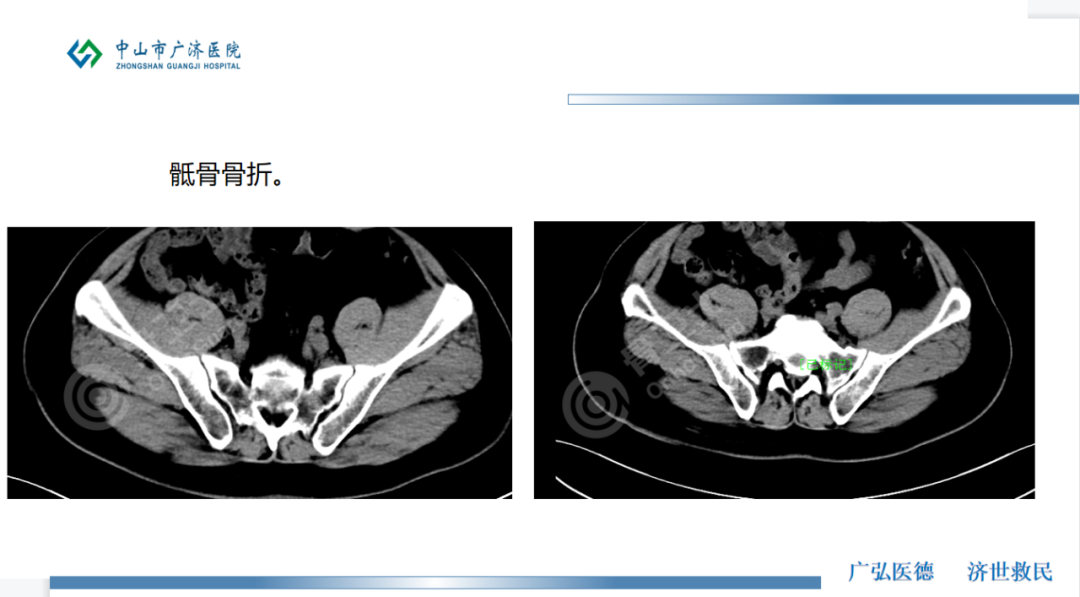

【入院诊断】左尺骨鹰嘴骨折,骶1椎体骨折,左侧骶骨翼多发粉碎性骨折,左肘部皮下血肿,全身多处皮肤软组织挫伤。

▲患者术前影像